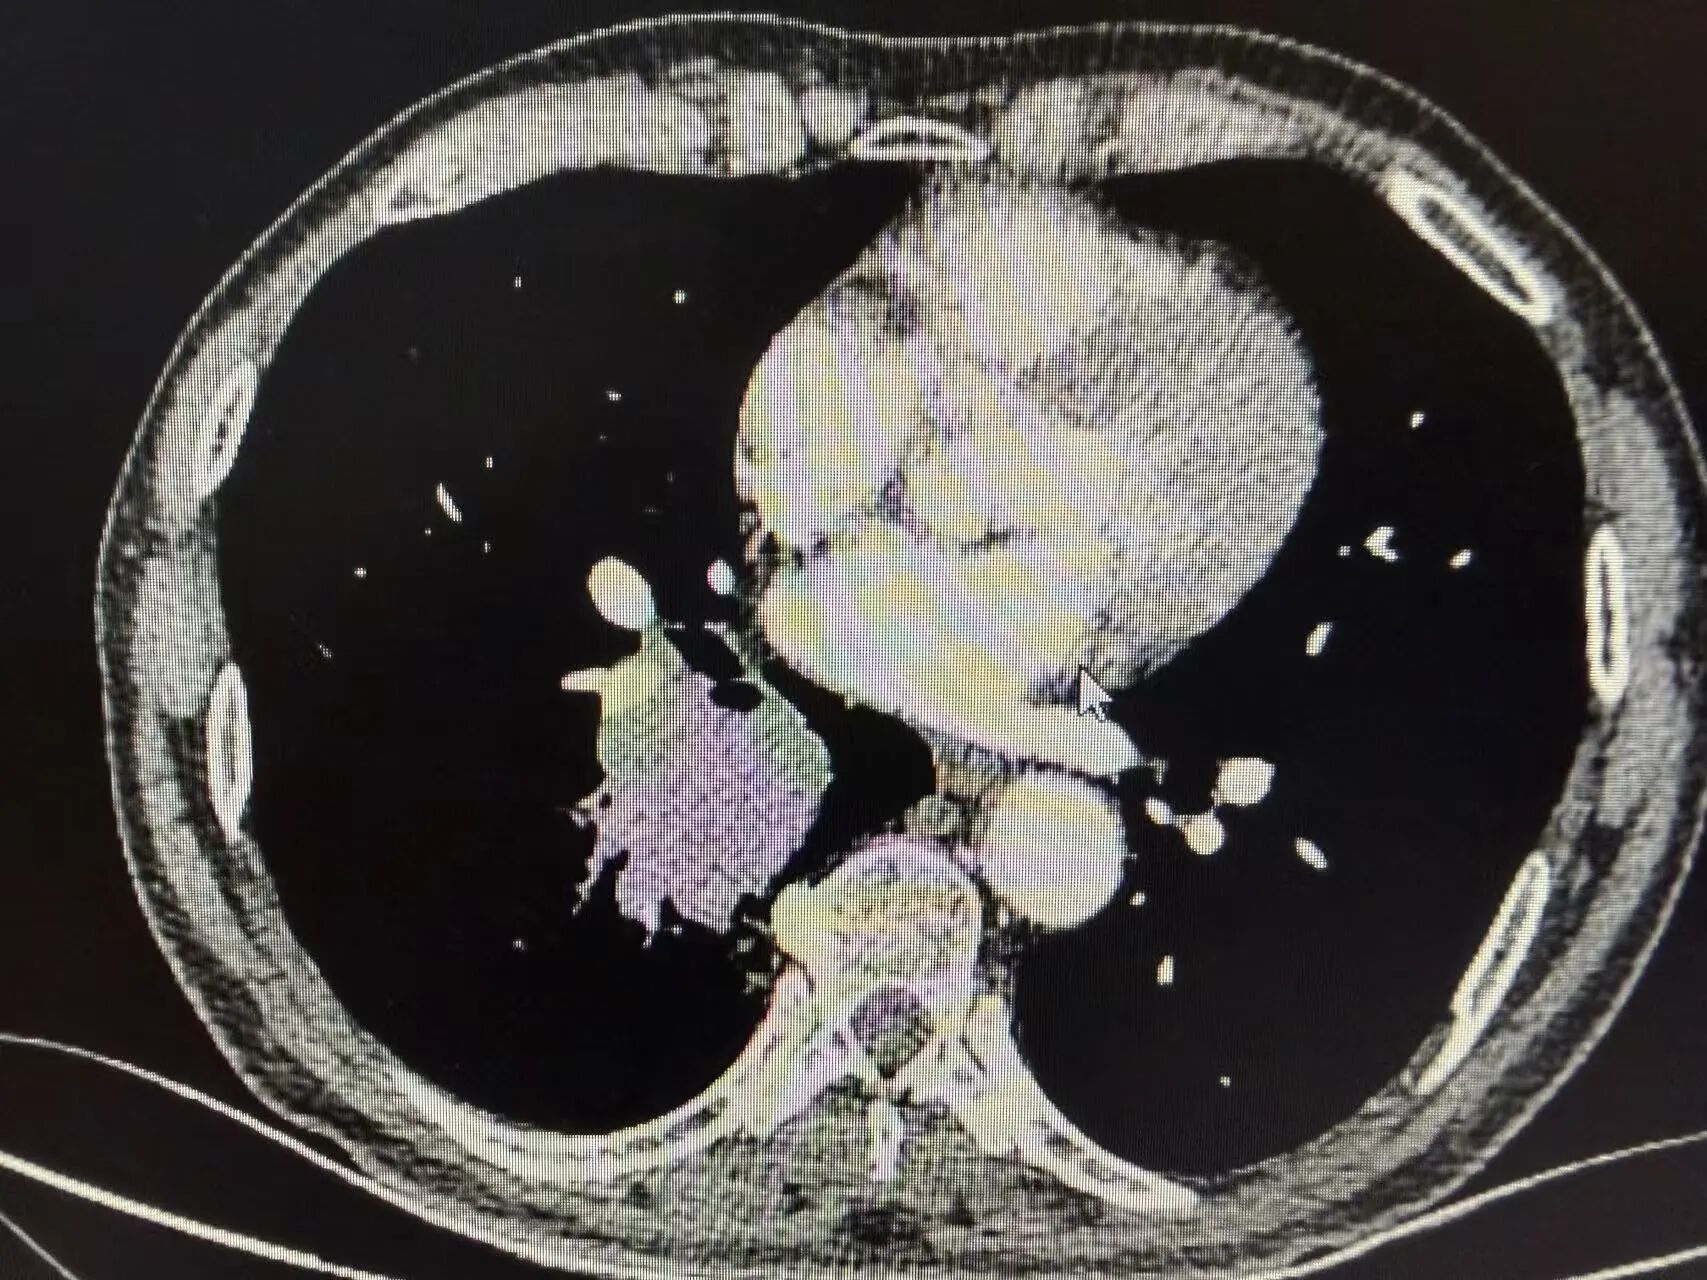

肿瘤明显退缩、手术条件明显改善后,我们为患者实施了单孔胸腔镜下右中下肺叶切除术

手术仅通过胸部一个小切口完成,创伤小、出血少、恢复快,术中顺利完整切除病变肺叶。

术后胸片显示右中下肺叶已切除,胸腔形态规整

引流管位置良好,肺部复张情况理想